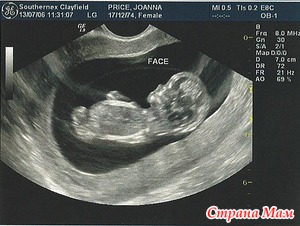

Когда тебе показывают этот комочек, который всего чуть больше 4см, но уже такой родной и любимый. Показали нашего малыша мне и покатились слезы

слезы радости! Виден каждый пальчик даже

Врач сказала, что малыш очень активный. На экране он очень шустро шевелился как мне показалось. Все развивается по сроку, никаких отклонений нет и это самое главное!!!

Узи я делала у одного из лучших узистов нашего города, врач генетик, очень милая женщина, все показала и рассказала мне, сделала несколько фоток малыша(муж пойти не смог, но фотки стал требовать прям с порога

Стала я так сказать подопытной у них. Снимали как происходит забор крови, повторно мне сделали узи на камеру(обычное и 3Д), сняли крупным планом малыша на экране

мы на узи были 47мм. теперь будем быстро рости